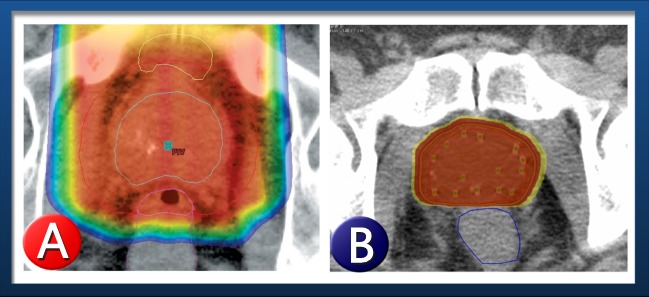

A. A dose map of a prostate being treated with protons shows the excess radiation deposited outside the prostate. This is what causes the higher side effects.

B. A similar dose map of a prostate being treated with a seed implant shows no excess radiation outside the prostate, as the seeds radiate the prostate from within.